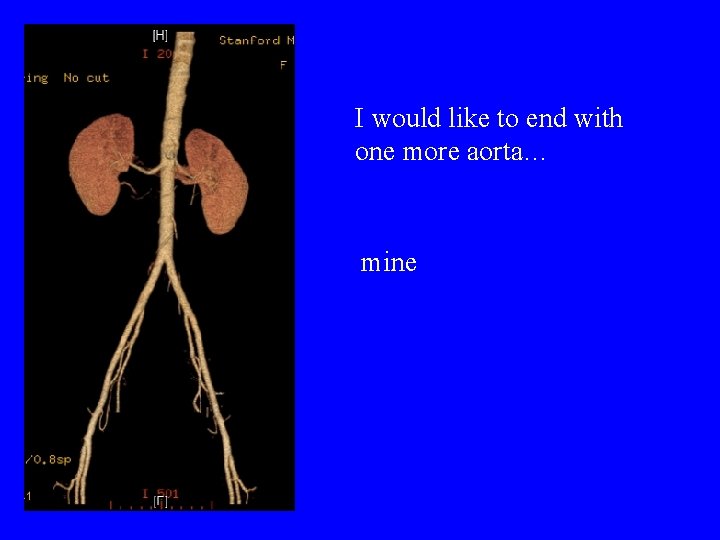

I would like to end with one more aorta… mine